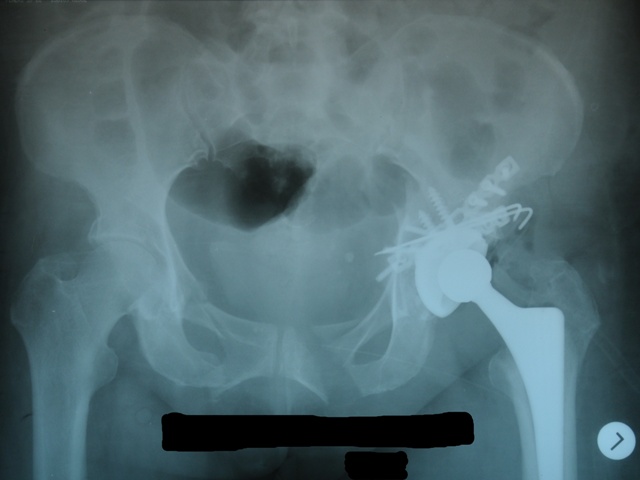

Пациентка  получила травму в результате ДТП, находясь внутри автомобиля. Травма получена 20.04.2011г. Сразу после травмы доставлена в Менделеевскую ЦРБ с диагнозом: Сочетанная травма. Множественные закрытые многооскольчатые переломы лонной, седалищной и подвздошной костей справа и слева, оскольчатый перелом дна и крыши вертлужной впадины слева с вывихом бедра. Закрытый перелом 8-10 ребер слева. Травматический шок 3-4 ст.

В Менделеевской ЦРБ были начаты противошоковые мероприятия. После стабилизации состояния, больная 28.04.2011г. была переведена в травматологическое отделение №2 ГАУЗ РТ БСМП. В травм. отд. №2 больной наложено скелетное вытяжение, проведены дополнительные исследования и подготовлена к операции. Установлено наличие у больной посттравматической невропатии седалищного нерва слева.

06.04.2011г. произведена операция остеосинтеза подвздошной и седалищной кости слева, остеосинтез заднего края и крыши вертлужной впадины,   тотальное бесцементное эндопротезирование левого тазобедренного сустава.

- Из переднего пахово-подвздошного доступа произведен остеосинтез  реконструктивной пластиной подвздошной и седалищной костей с  репозицияей  и фиксацией передней

коллоны вертлужной впадины.

- Из заднего доступа произведена репозиция и фиксация крыши и заднего края вертлужной впадины реконструктивной пластиной, а так же тотальное бесцементное эндопротезирование тазобедренного сустава.Между «вкладышем» чашки вертлужного компонента и самой вертлужной впадиной использован аутотрансплант из костной стружки. Была так же произведена ревизия седалищного нерва – нарушения целостности нерва не выявленно.